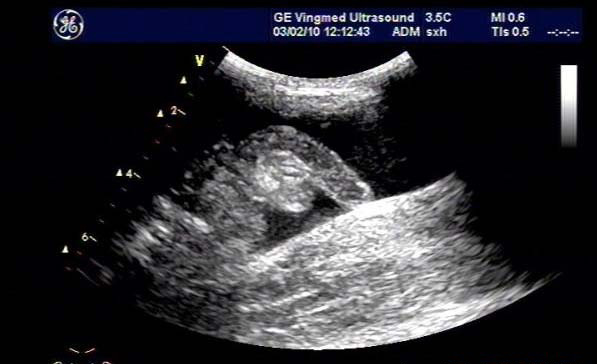

闌尾炎是美國兒童常見的疾病,發生率持續增加;雖然CT是最常用來評估疑似闌尾炎患者之癥狀的影像技術,但它與顯著增加放射線暴露有關,而超聲檢查不會有放射線暴露。

研究目標是,兒童急性闌尾炎時,使用超聲檢查作為第一種影像檢查方式時,確認是否會增加復雜性闌尾炎比率與住院天數(LOS)。